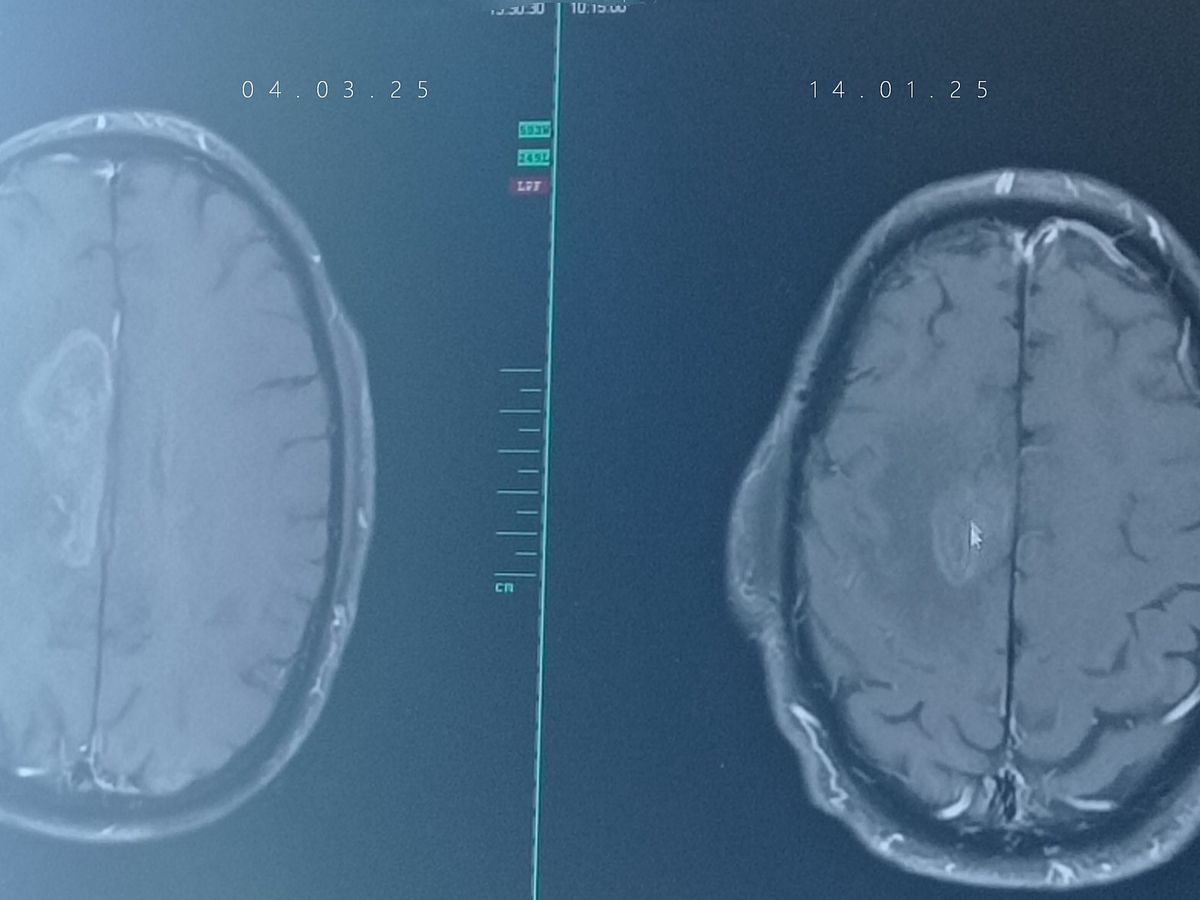

Nach der ersten Operation folgten Bestrahlung und Chemotherapie, doch der Tumor wuchs erneut. Eine zweite Operation leider dadurch halb gelähmt, mittlerweile wieder aber so gut wie es geht wieder am laufen.. weitere Chemotherapien sowie die Behandlung mit Stivarga schienen Hoffnung zu geben, doch leider zeigen die letzten Untersuchungen wieder Zellwachstum.

Die Nebenwirkungen von Stivarga sind jedoch extrem belastend und machen ihn mehr zu schaffen als die vorherige Behandlung. Am 14.02 der erneute MRT Termin sieht wohl auch nicht so gut aus, das wieder Krebszellen zusehen sind. was weiter hin auf uns zu kommen wird können wir nicht sagen. Trotz allem kämpfen wir weiter – Tag für Tag. Wir sind dankbar für jede Unterstützung und jede gute Erinnerung, die uns hilft, die schwere Zeit zu überstehen.